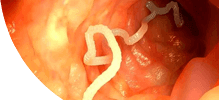

- Паразитларни фалаж қилади ва тухумларини 48 соат ичида йўқ қилади

- У танадан ажралиб, 2-3 ҳафта ичида танадан чиқариб ташланади